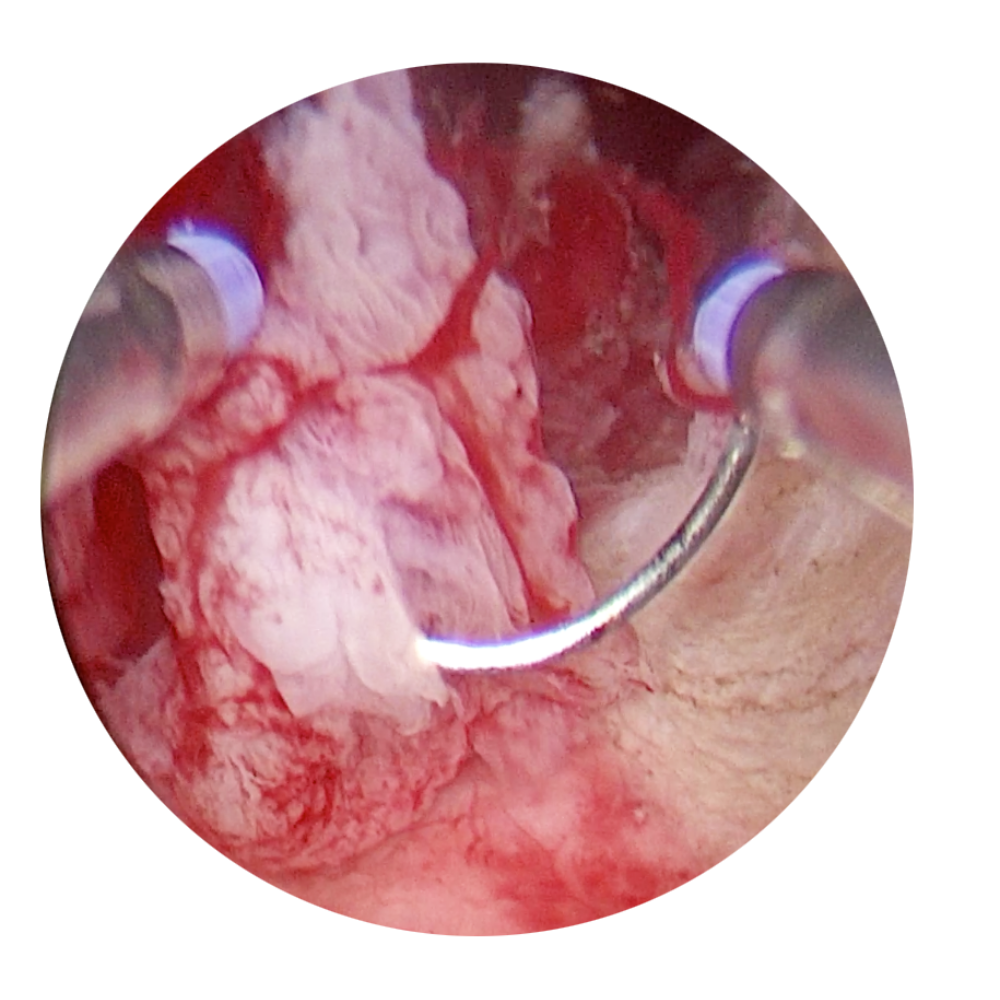

ReseCare

Deux modèles de résecteurs 6mm et le respect de toutes les femmes

Les avantages de ce faible diamètre sont nombreux, aussi bien pour le praticien que pour la patiente.

Avec ReseCare, votre geste opératoire est précis mais aussi plus rapide puisque les étapes de dilatation sont moins nombreuses. Aussi, les copeaux étant de petite taille, leur présence est moins pénalisante pour votre vision et votre confort de travail.

ReseCare respecte vos patientes. La résistance à l’introduction est naturellement réduite et le passage facilité, même chez les femmes ménopausées ou avec un col sténosé. De ce fait, le volume de liquide absorbé par la patiente est moindre et confirmé par un bilan entrée/sortie systématique.L’utilisation d’instruments 3mm sans énergie préserve l’endomètre de vos patientes. Même dans le cadre de pathologies majeures telles que les fibromes calcifiés de grandes tailles ou des cloisons utérines complètes, la performance de ces instruments rigides vous permet une prise en charge rapide et efficace.